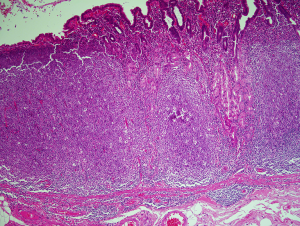

Structurally the lymphoid tissue in the gut mucosa consists of a lymphoid follicle with a reactive germinal centre that has the dark zone at the base with the light zone closest to the mucosal surface (Figure 2A). The germinal centre is surrounded by a well formed mantle zone that contains predominantly IgD positive naïve B cells and which is thickest below the surface epithelium and is rather thin where it abuts the muscularis mucosae (Figure 2B). External to this is the marginal zone that consists predominantly of slightly larger B cells with more abundant pale cytoplasm. There are other cell types in the marginal zone including plasma cells, T cells, macrophages and dendritic cells. This zone is also more developed below the surface where epithelial crypts are absent. The marginal zone abuts the overlying dome epithelium with infiltration of the epithelium by marginal zone B cells forming a lymphoepithelium (Figure 2A,C).